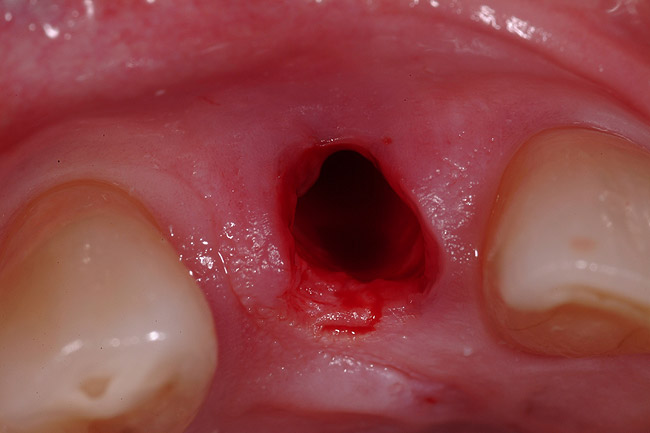

A 54-year-old, non-smoking woman presented with a root fracture at the maxillary right lateral incisor (Figure 1). The patient presented with a 10-mm pocket at the mid-facial probing depth, and a Grade 2 mobility. The preoperative peri-apical digital radiograph can be seen in Figure 2. A natural diastema existed on the distal aspect of the right maxillary incisor, and the patient did not wish to have this corrected. To hold the natural tissue emergence profiles throughout the treatment phase, the immediate implant placement and provisionalization procedure was chosen to treat the affected site. Before the procedure, an occlusal index and registration was taken so that when the retrofitting of the natural tooth shell was accomplished, the exact location of the natural tooth shell could be seated on the implant abutment at the time of implant placement (Figure 3). After administration of an appropriate local anesthetic, tooth No. 7 was removed by an atraumatic technique to preserve the natural soft tissue emergence profiles present pre-surgically (Figure 4). After tooth removal, debridement of the extraction socket was accomplished by curettage of the socket, followed by rotary instrumentation with a course #8 round diamond to ensure removal of all remnants of the periodontal ligament, granulation tissue, and localized debris. To aid in the debridement, the patient was started on a preoperative administration of Augmentin 875 mg, taken the day before treatment, and once again 1 hour before the surgical visit. The patient then continued this antibiotic course for a total of 10 days.

Figure 4  Atraumatic tooth removal.

Figure 4